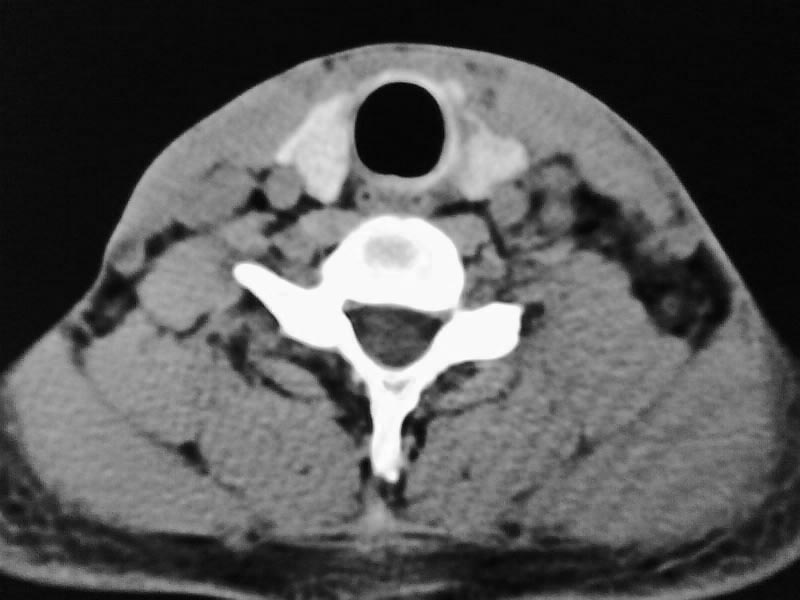

以下是引用余辉在2009-5-3 11:36:00的发言:[br]左侧胸锁乳突肌下方不规则肿物影,边界不清,内部密度不均,左侧颈外侧区脂肪增多,多发淋巴结肿大,考虑淋巴或神经来源肿瘤可能性大,不除外淋巴结炎,肌源性肿瘤及增生性肌炎等,活检